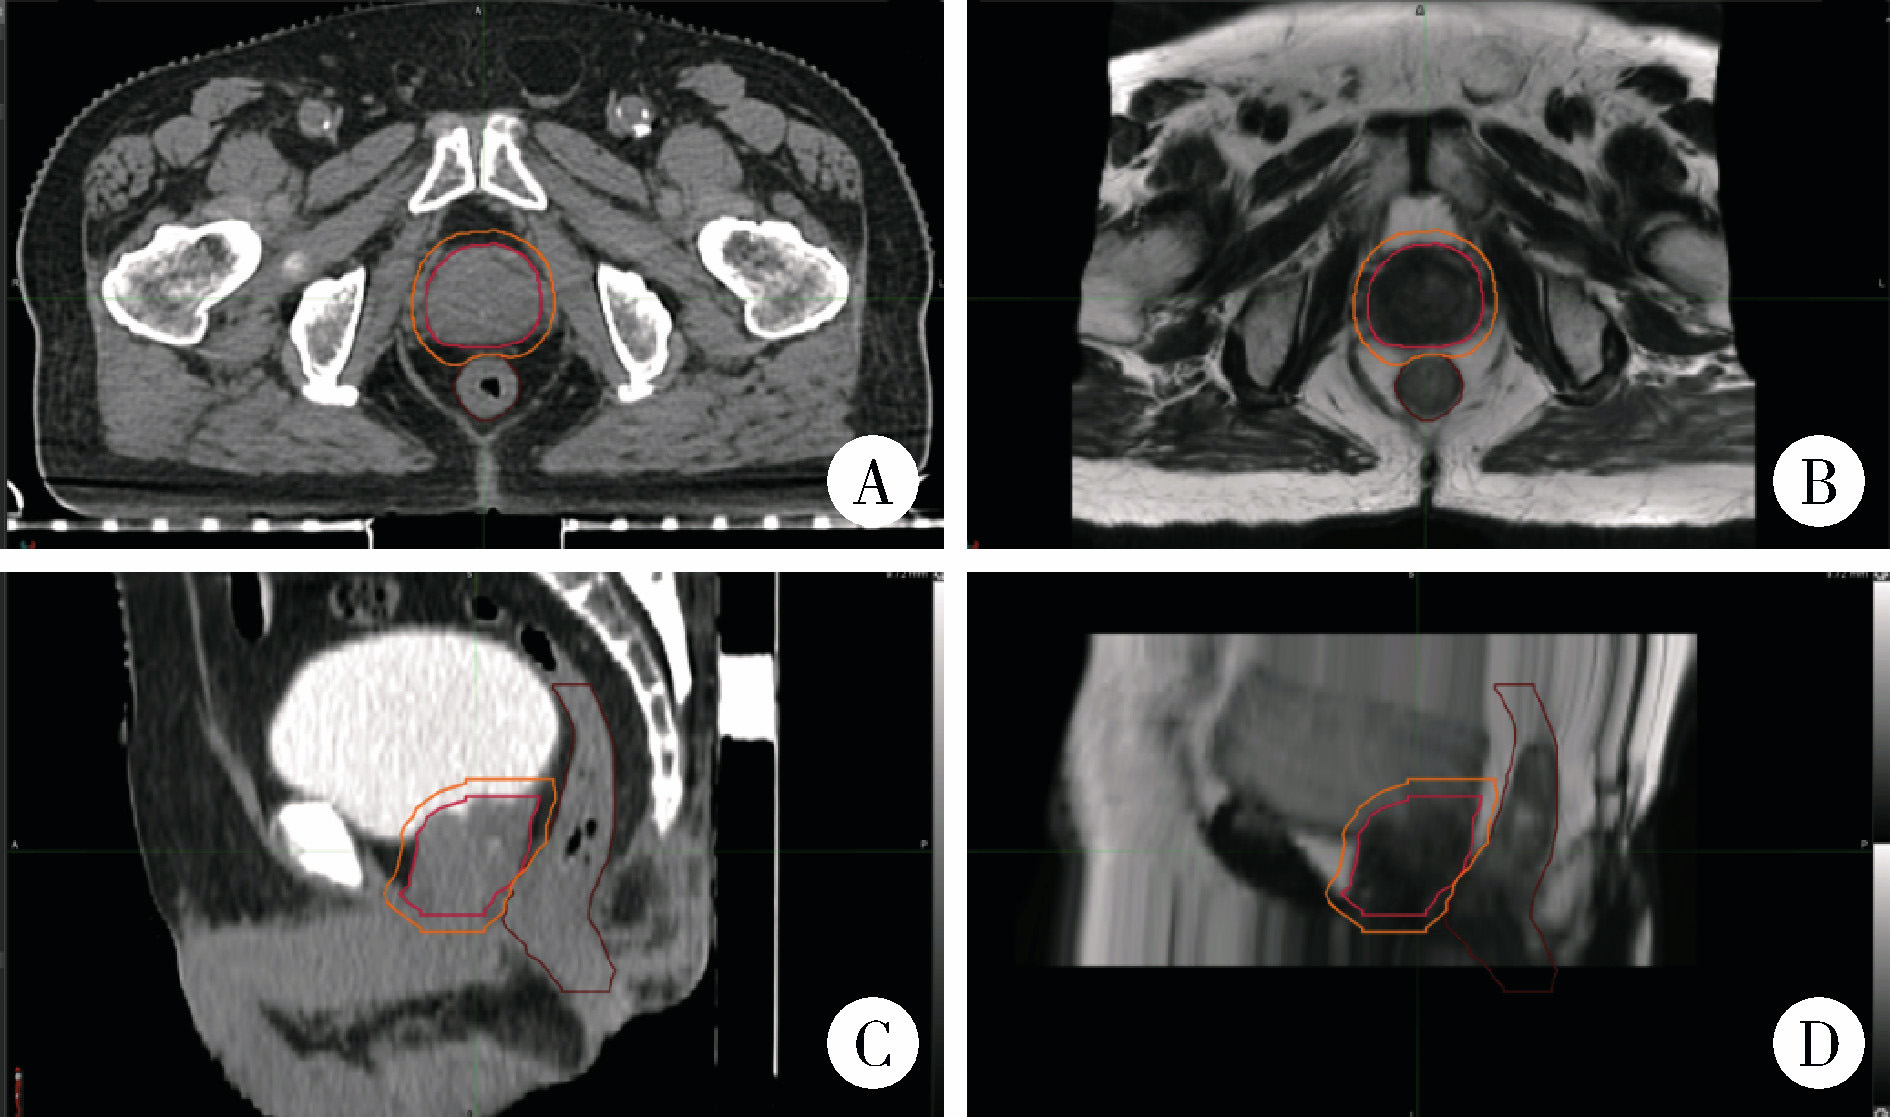

Comparison of setup errors between two immobilization methods in prostate cancer radiotherapy based on cone-beam computed tomography